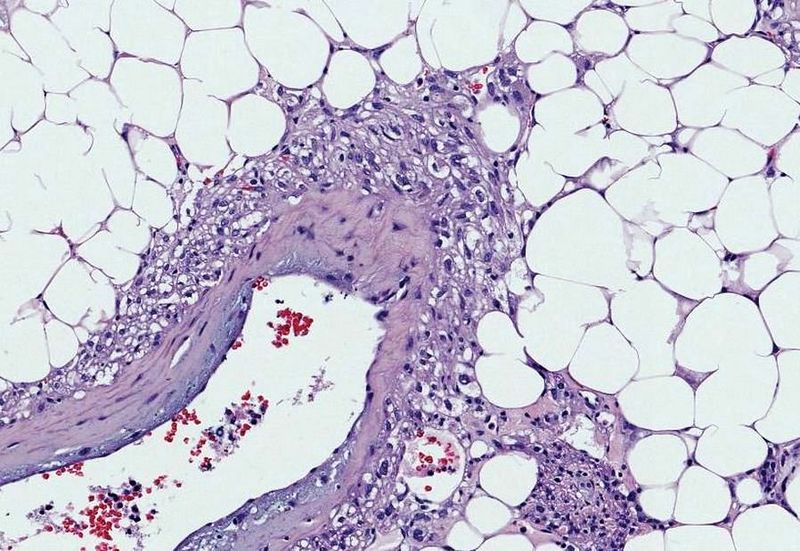

Urothelial Carcinoma

Urothelial carcinoma is also known as transitional cell carcinoma.

The epithelial lining of the renal pelvis, ureter, bladder, or urethra is the source of this malignant tumor.

Urothelial carcinoma is the most typical type of bladder cancer.

Risk factors for urothelial carcinoma include:

- Cigarette smoke (major risk factor)

- Naphthylamine

- Azo dyes

- Cyclophosphamide

- Phenacetin

The typical presentation of urothelial carcinoma is painless hematuria in an adult.

Urothelial carcinoma arises via two distinct pathways:

- Flat

- Papillary

Flat urothelial carcinoma is characterized by the invasion of a high-grade flat tumor and is associated with p53 early mutations.

Papillary urothelial carcinoma initially appears as a low-grade papillary tumor, advances to a high-grade papillary tumor, then invades, and is not linked to early p53 mutations.

A field defect is when a tumor recurs and is frequently multifocal in nature.